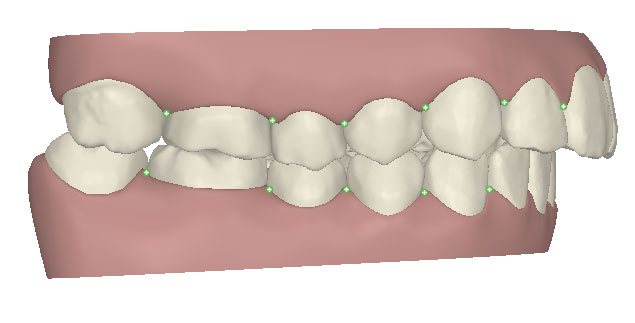

コンピューターを使って作製した透明なマウスピース型の矯正装置(アライナー)を段階的につけ替えていき、それにより歯列を矯正し、歯並びへと改善します。はじめに 治療開始から終了までのアライナーができあがってきます。マウスピース型矯正装置(インビザライン)の最大の特徴として「クリンチェック」というソフトがあります。3D のコンピュータ シュミレーション画像で、治療開始から完了までを目で見て確認することができます。

マウスピース型矯正装置(インビザライン)治療においては、クリンチェックというシミュレーションソフトを活用しております。

このクリンチェックの魅力は、治療前の現在の歯並びから治療後の歯並びを視覚化して患者様にご説明できる点にあります。

また、抜歯・非抜歯、全体矯正・部分矯正などそれぞれの治療パターンをシミュレーションすることが可能です。